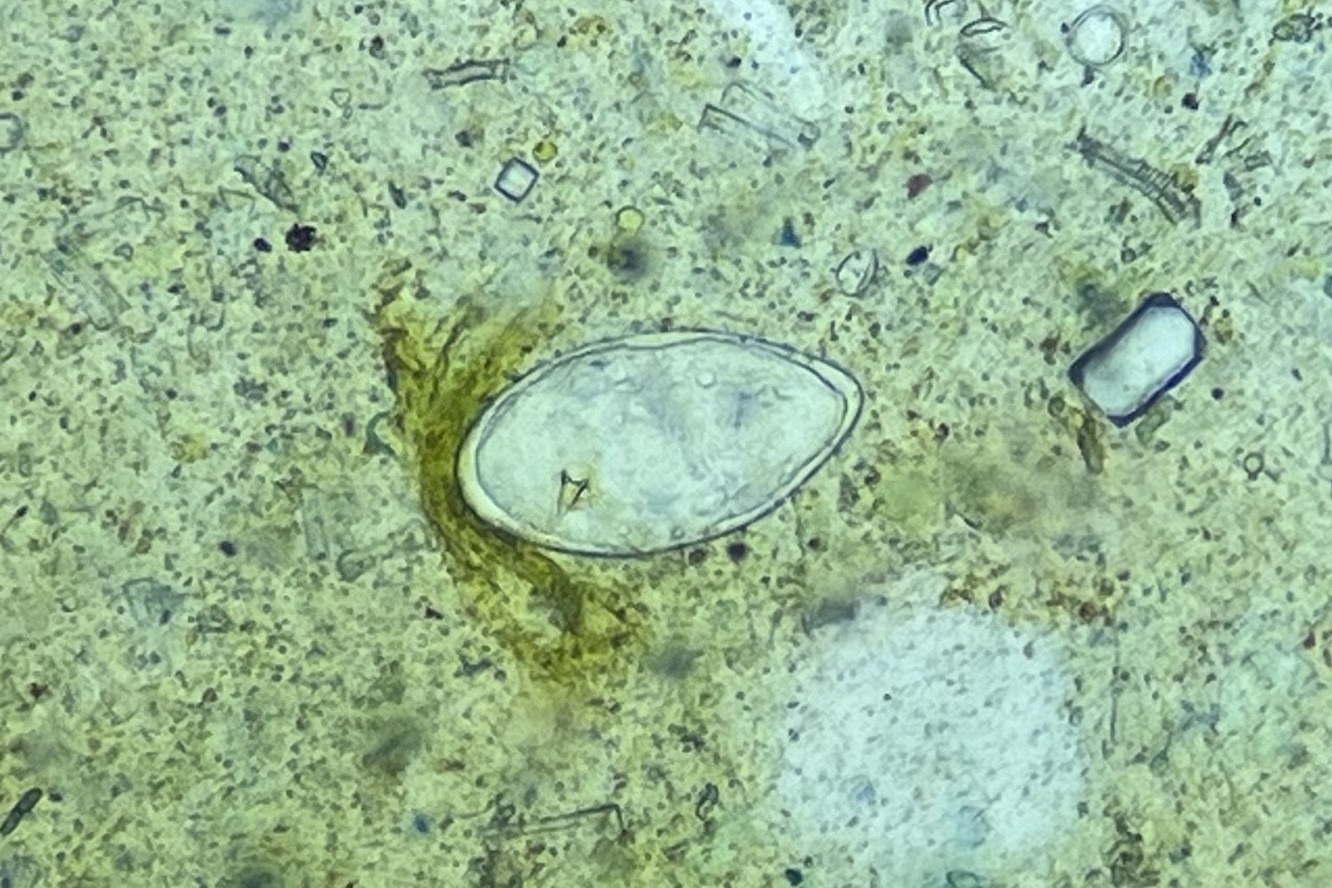

현장 실험실에서는 우리 협회 전문가와 카메룬 보건요원이 함께 검경 작업을 진행하며

전체 대변 검체 3,275건 중 1,917건(54.8%)의 기생충 감염 여부를 분석했어요.

조사 결과, 일부 보건지구에서는

주혈흡충(SCH)과 토양매개성 기생충(STH) 감염이 여전히 높은 수준으로 확인되었으며,

향후 집중 관리가 필요한 고위험 지역을 명확히 식별할 수 있었습니다.